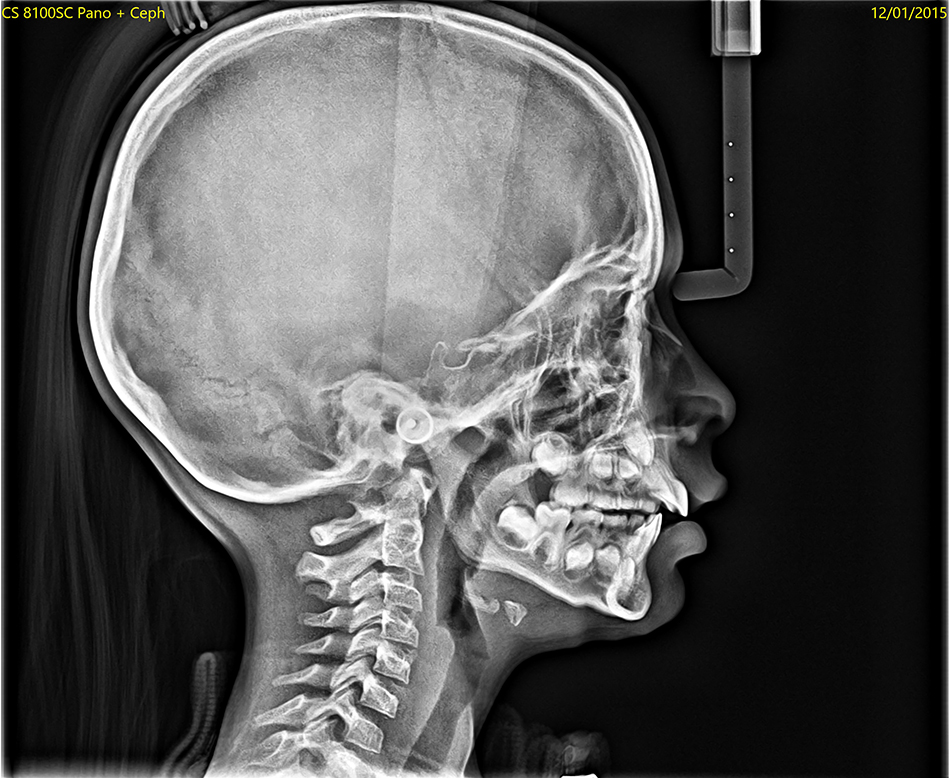

В клинике PRF мы используем современное стоматологическое компьютерное томографическое оборудование CS 8200 3D, которое обеспечивает детальные трёхмерные изображения структуры ваших зубов и челюстей.

Трёхмерные изображения позволяют рассмотреть мельчайшие детали, включая потенциальные патологии, и выбрать наиболее подходящий план лечения. Данная технология особенно эффективна при анализе прикуса, в дентальной имплантологии, пародонтологии, выявлении новообразований, зубном протезировании, а также в челюстно-лицевой хирургии.

Использование 3D конусно-лучевой компьютерной томографии значительно улучшает планирование лечения. Как стоматолог, так и челюстно-лицевой хирург получают точное представление о корнях зубов, костных структурах и возможных изменениях, которые трудно обнаружить с помощью обычных рентгеновских снимков.